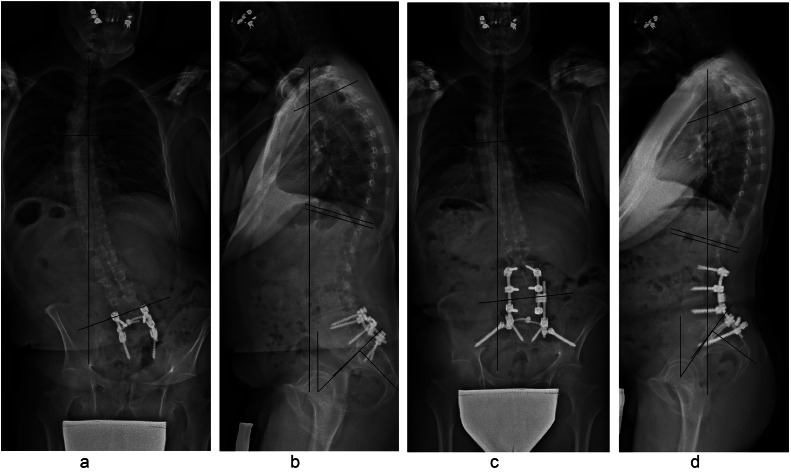

Fig. 2.

Sixty-five y old patient with degenerative lumbar kyphosis. Preoperative full spine anteroposterior and lateral X-ray showing a lumbar kyphosis with compensatory distal thoracic lordosis and pelvic retroversion (A and B), C7-CSVL=0.2 cm, coronal Cobb=11°, PI=43°, PT=46°, SVA=7 cm, LL=+13°, thoracic kyphosis (TK)=7° Postoperative full spine anteroposterior and lateral X-ray after L4 modified PSO including the disc above and demonstrating restoration of lumbar lordosis, thoracic kyphosis and pelvic tilt (c and d), C7-CSVL=1.2 cm, coronal Cobb=0°, PI=43°, PT=31°, SVA=0 cm,LL=−42° (55° of total improvement), TK=45°